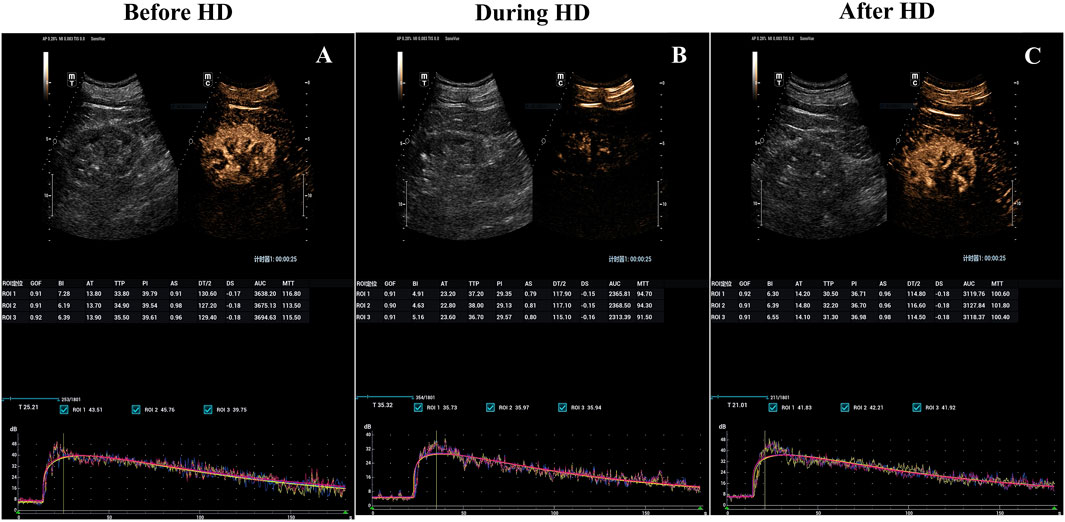

All enrolled patients (30/30, 100%) successfully underwent CEUS, without any microbubble-related adverse events observed. Average baseline PI was 38.37 ± 5.23 (mean ± SD). At peak stress (3 h after HD initiation), average PI dropped to 82.47% ± 12.43% of baseline. After HD, average PI recovered to 94.67% ± 8.74% of baseline (Table 2; Figures 1, 2). Repeated measures ANOVA with post hoc testing demonstrated that the intradialytic PI drop was statistically significant compared with pre- and post-HD (P < 0.001).

Figure 1

Three panels labeled A, B, and C show ultrasound images of a kidney before, during, and after hemodialysis (HD), with dual grayscale and color contrast. Each panel includes tables with measured parameters and graphs illustrating data trends over time.

Figure 1. Hemodialysis-induced decrease in kidney blood flow visualized with parametric renal perfusion maps. Renal blood flow at baseline (A), 3 h into (B) and 15 min after hemodialysis sessions (C) for the incident hemodialysis patients with a preserved RRF. RRF, Residual renal function.